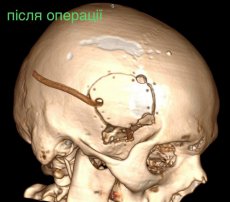

У Волинській обласній дитячій клінічній лікарні прооперували 16- річного юнака з травмою головного мозку. І травма ця дуже незвичайна – у хлопця була куля в голові, що призвела до руйнації скроневої кістки та частини головного мозку.

Лікарі виконали невідкладну операцію і вилучили стороннє тіло, видалили пошкоджені тканини і відновили цілісність збережених тканин.

«Добре, що куля зупинилась в 1 см від надзвичайно важливої судини і права скронева частка (яка пошкодилась в результаті травми) - функціонально незначима. Інакше, наш козак був би зовсім іншим, навзавжди», - пише лікар.